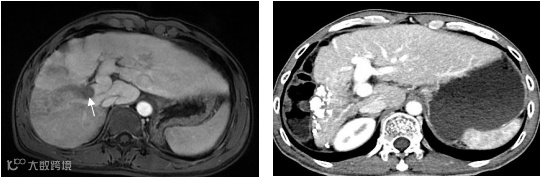

图4.该例肝右叶巨大肝癌合并门静脉右支癌栓(左图,箭头示癌栓),采用TACE治疗肝内肿瘤和放射性粒子治疗门静脉癌栓,术后19个月肝右叶肿瘤几乎完全坏死缩小,而粒子阻止了癌栓进展到主干,门静脉主干保持通畅(右图),现患者已生存5年